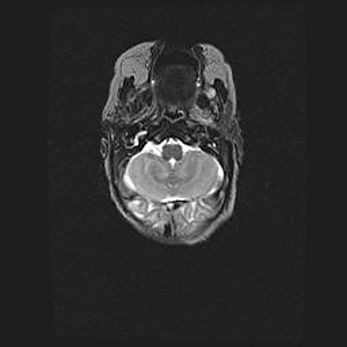

Подострая гематома правой гемисферы мозжечка.

Наружная гидроцефалия.

Возраст: 15 дней

Вес: 3100 г

Пол: женский

Окружность головы: 37 см

Срок гестации: 35-36 недель

При открытой наружной форме гидроцефалии у новорожденных расширяются и переполняются субарахноидные пространства.

Кровоизлияния в мозжечок имеют две клинико-анатомические формы: полушарные гематомы и кровоизлияния в червь.

К появлению этой патологии может привести: повреждения головного мозга, возникающие в результате асфиксии и гипоксии плода при беременности, или травмы во время родов. Редко гематома мозжечка может быть результатом первичной коагулопатии и сосудистой мальформации, диссеминированном внутрисосудистом свертывании, изоиммунной тромбоцитопении.